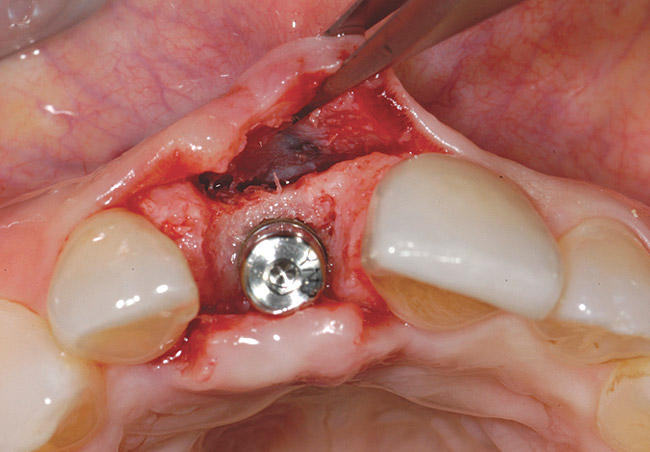

Figure 12  Stage I surgery (implant shown with healing abutment), 4 months after extraction and socket graft.

Figure 12

Figure 13  Primary flap closure.

Figure 13